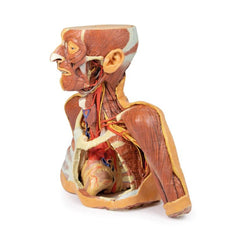

3D Printed Superficial Facial Nerves & Parotid Gland

This 3D model presents the superficial anatomy of the face and head, and compliments the superficial facial anatomy

of our HW 44 model with a more expanded dissection across the scalp and occipital regions.

The superficial

neurovascular and muscular structures in the face largely mirror the structures described in reference to our HW 44

specimen (see description), although the terminal branches of the facial nerve (CNVII) can be largely followed

across a longer course from the parotid gland and the platysma muscle has been retained superficial to the mandible

and extends towards the neck.

In contrast to the HW 44 specimen, this model has a more expansive superficial

dissection inferior to the external ear and across the posterior scalp and occipital region. This allows for an

expanded appreciation of the neurovascular distribution of the supraorbital and supratrochlear nerves and arties

with the superficial temporal artery. Inferior to the ear, the retromandibular vein has been exposed with the

ascending fibres of the great auricular nerve on its superficial surface (and further branches of this nerve on the

surface of the sternocleidomastoid muscle). At the posterior border of the sternocleidomastoid muscle the lesser

occipital nerve is just preserved, near the exiting and ascension of the occipital artery and vein near the

trapezius muscle towards the posterior scalp. Surrounding the external ear are fibres of the auricularis superior

and posterior muscles. Near the margin of the dissection window posteriorly the deep fibres of the occiptalis muscle

can be seen integrated into the epicranius (occipitofrontalis) muscle.